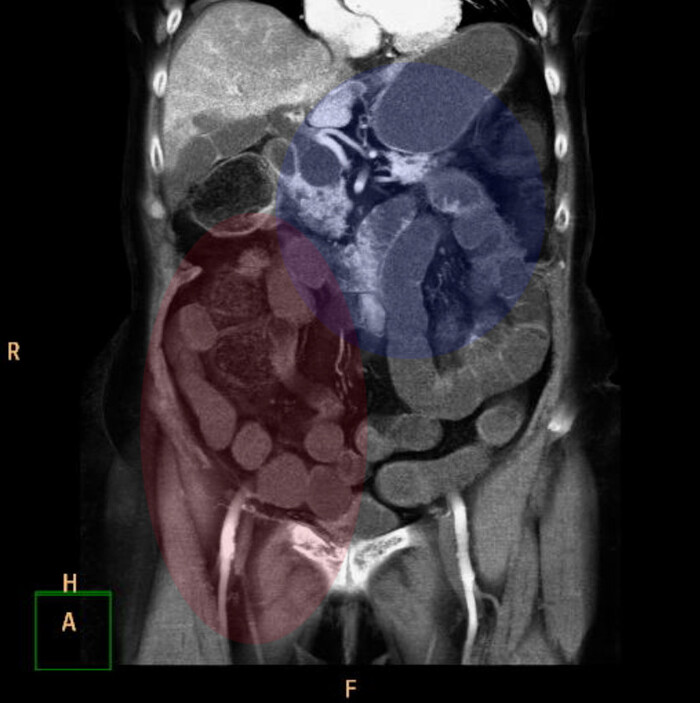

В лёгочном окне - очаги консолидации ("уплотнения" лёгочной ткани) в постеробазальных (задне-нижних) отделах правого лёгкого (на ренгенснимках и КТ, а также МРТ та часть, что на мониторе расположена слева - всегда правая сторона пациента). На последнем снимке серии ниже (сагиттальная или боковая реконтрукция) были непонятные артефакты, как от металла:):

Переключаемся на "костное" окно (позволяет луче оценить кости и прочие плотные структуры), где реально видим "металлический" предмет в просвете правого нижнедолевого бронха:

сагиттальная, аксиальная и корональная реконструкция